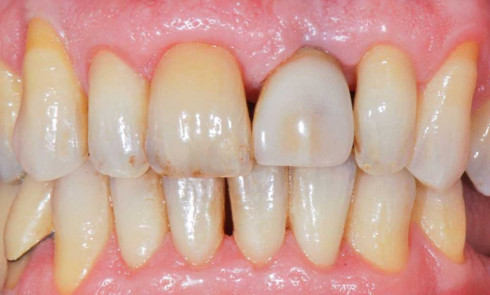

Cliniquement, la parodontite se manifeste par une atteinte du parodonte superficiel et profond : gencive œdématiée avec saignement provoqué au...